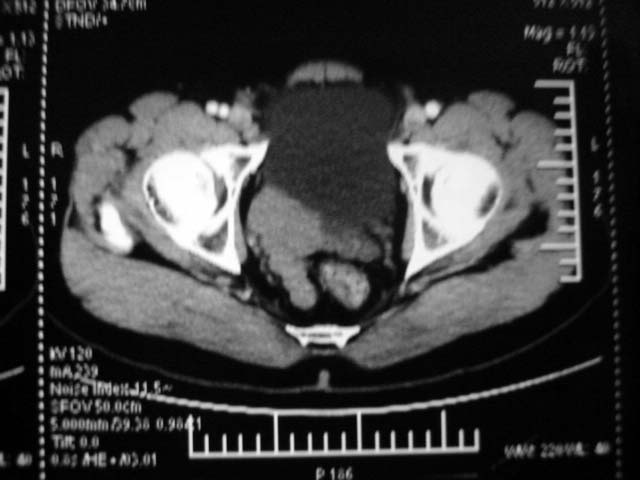

标题: CT15740B:(续)增强片。

ct15740:m45y,膀胱右后方占位?

增强看右侧精囊腺不规则增大,均匀强化,膀胱精囊三角消失,还是考虑精囊腺占位。

肿块与膀胱成锐角.不是膀胱占位

强化程度不符合肾脏的特点,不考虑异位肾。

小肠肠管可能性大。

喝碘水或排空尿后俯卧位也许会有帮助。

膀胱右后侧占位性病变,建议手术。